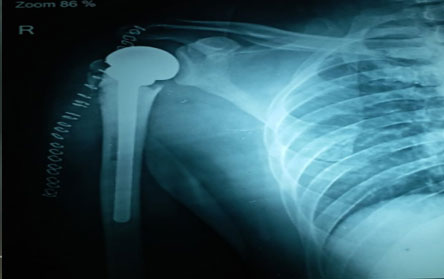

The Center of Orthopedics KUMAR ORTHO HOSPITAL ,Patna, offers the entire spectrum of modern orthopedic management, which is effective, patient - friendly & result oriented. In a nutshell, it is one stop treatment for all orthopedic ailments and fractures with emphasis on avoidance of complications, rapid mobilization, decreased period of confinement and an early return to normalcy.